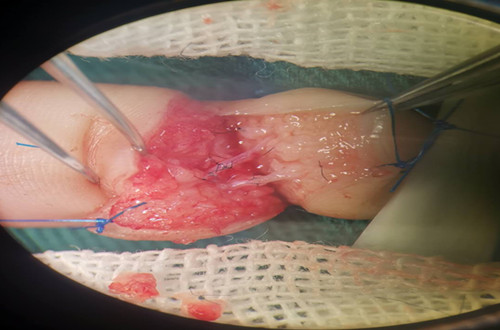

手術資料如圖示:

侯曉進主任帶領醫師岳賢峰、魏石磊歷時2小時,成功再植離斷指體。觀察指體張力適中,皮溫、皮色正常,毛細血管充盈實驗正常。術后予以對癥治療,按時傷口換藥,保持清潔。再植指體存活良好。于2019年1月22日間斷拆除傷口縫線后,患兒治愈出院。